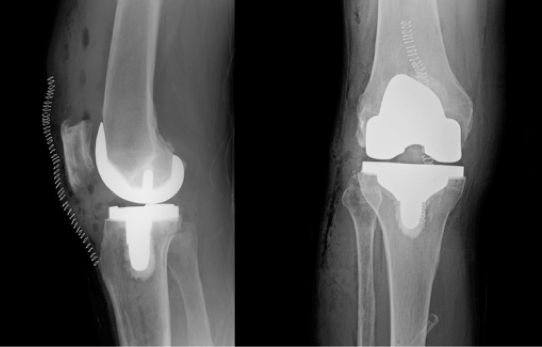

Based on the severity of the arthritis in the knee, total or partial knee replacement may be recommended by a surgeon. Both procedures involve the orthopaedic surgeon guiding the Mako Robotic-Arm to remove diseased bone and cartilage.

In comparison, Mako Robotic-Arm Assisted Total Knee replacement is a treatment option for adults living with mid to late-stage osteoarthritis of the knee. With Mako Total Knee replacement, the entire knee joint is replaced and the surgeon inserts a Triathlon Total Knee implant. With over a decade of clinical history, Triathlon knee replacements are different than traditional knee replacements because they are designed to work with the body to promote natural-like circular motion.